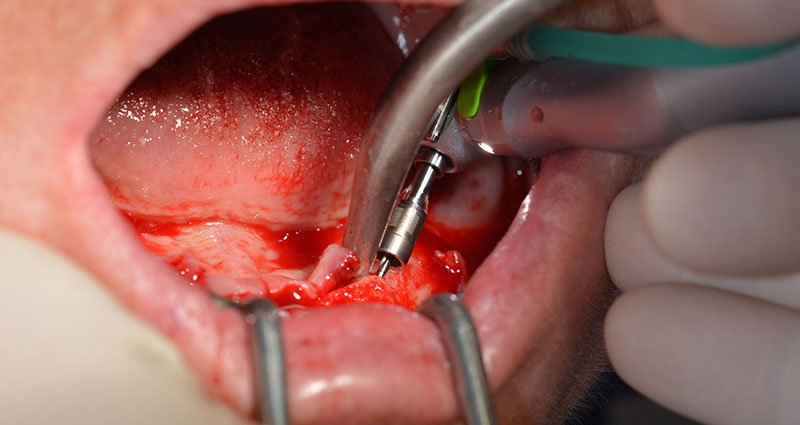

A continuación, se identificó el agujero mentoniano (foramen mentale) como la estructura anatómica límite y se alisó el cortical de la cresta ósea con la pieza de mano recta y una fresa redonda grande (fig. 4).

Es en este momento, donde se hacen patentes las primeras ventajas de Implantmed. El protocolo quirúrgico ya está predefinido y guardado en distintas posiciones fijas que pueden seleccionarse con solo pisar el pedal en la posición «P» o desde la propia pantalla. En este caso, la pantalla iluminada también muestra en grande la velocidad de 35 000/rpm preajustada en la posición 1 (figs. 5 y 6).